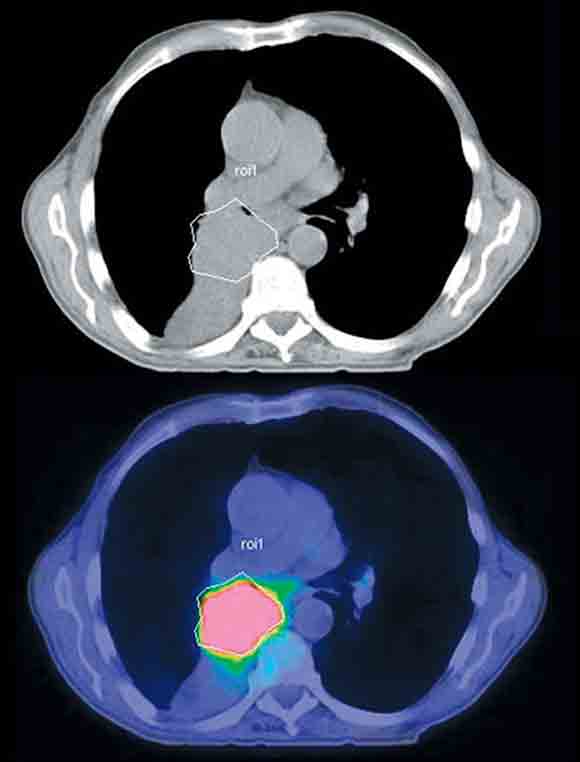

6 Positron emission tomography/computed tomography guided biopsy of a left scapular soft tissue mass

Such images allow representative histological sampling of the most metabolically active region within a heterogeneous mass lesion.

Attempts at histological characterisation can be problematic in patients with cancer. The availability of anatomical information from PET/CT can assist in selecting the most accessible mass for biopsy. After treatment, residual masses may not contain any active tumour, and the presence of residual uptake can guide which masses require biopsy. In addition, tissue heterogeneity is a common feature within individual malignant masses, particularly in sarcomas, where high-grade tumour can co-exist with acellular matrix components and low-grade tumour elements. Because of the high uptake of FDG in aggressive tumours, intermediate FDG uptake in low-grade tumours and very low FDG uptake in necrotic or fibrotic tissue, PET/CT imaging can be used to guide biopsy to the most metabolically active regions of structural masses (Box 6). This has two potential advantages: the likelihood of non-diagnostic biopsy may be reduced,16 and the biopsy will more likely reflect the most biologically active, and therefore prognostically significant, tumour elements.17,18